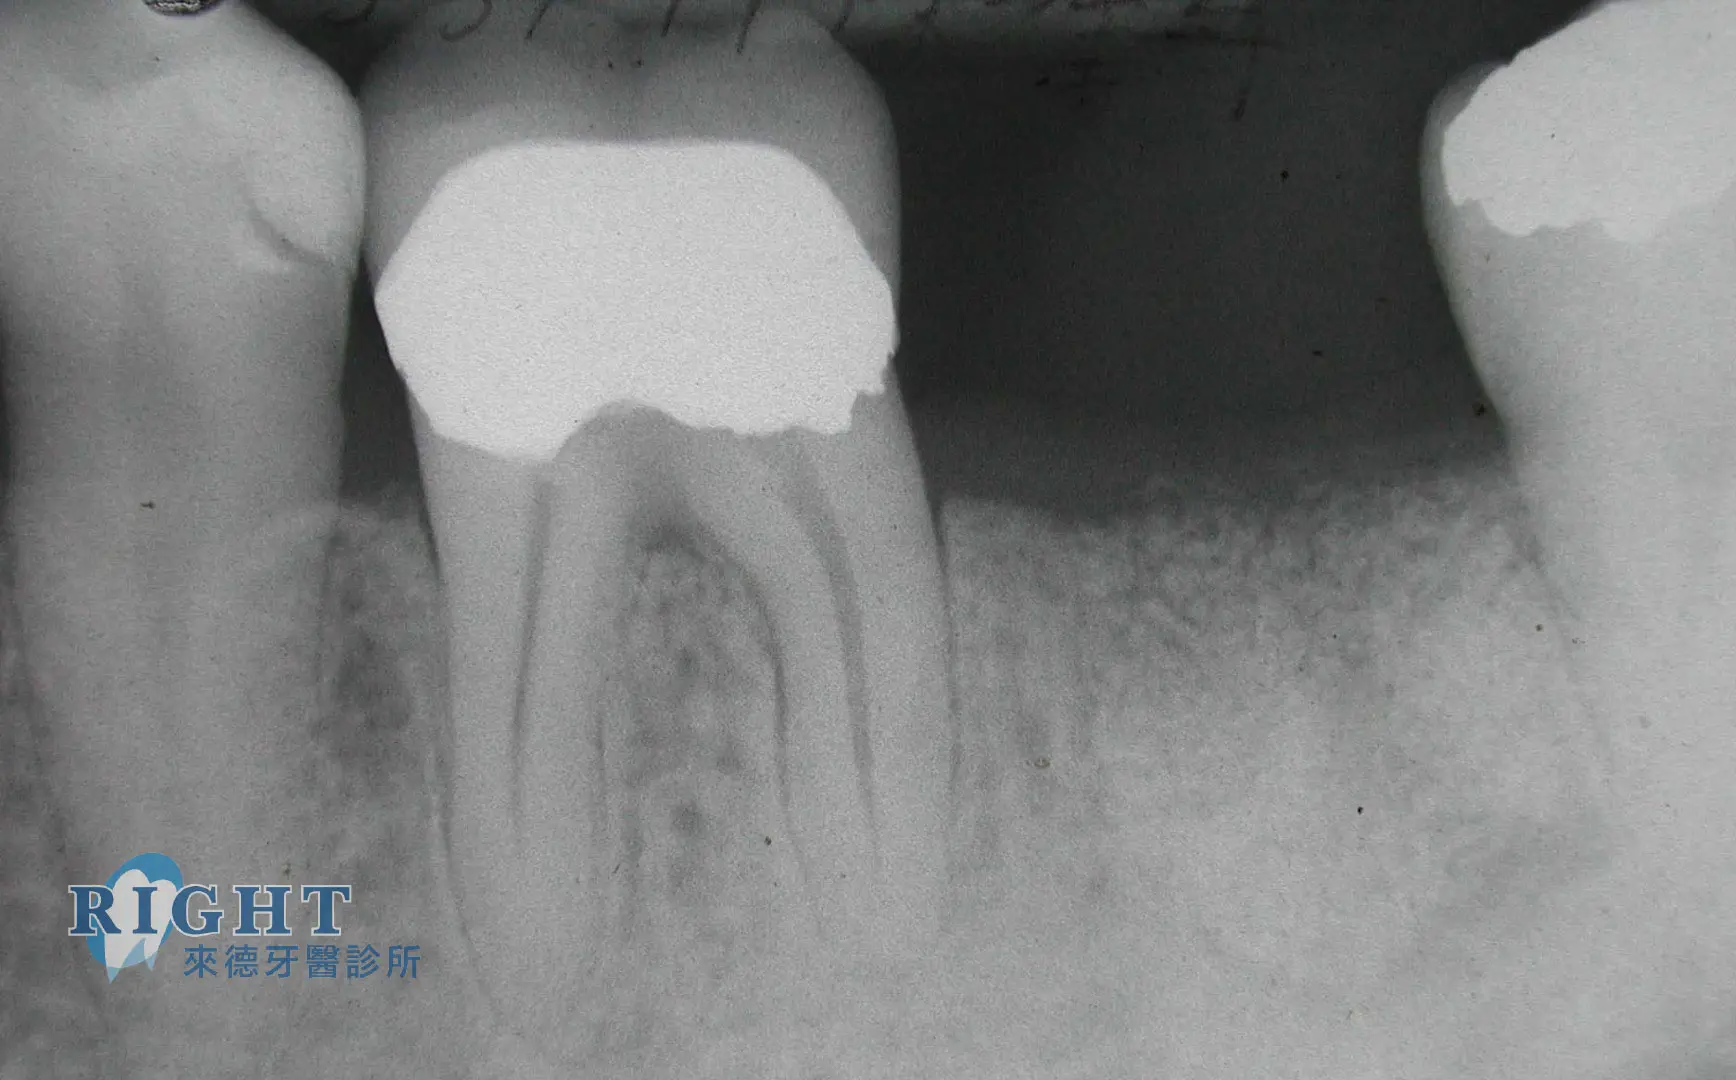

抽神經原因是甚麼?使用顯微根管治療有什麼好處?

當聽到醫師說要抽神經,相信各位患者都會瞬間如大難降臨,巴不得抽神經過程盡快完成,然而抽神經是項複雜度高的手術,不僅馬虎不得,以往醫師更需要依靠自身經驗來避免抽神經失敗風險,現在科技進步,有了顯微儀器的輔助,對於抽神經的風險也能有所降低。對於抽神經原因、一般抽神經方式與顯微根管的必要性等疑問,讓台北顯微根管醫師推薦-來德牙醫張崇翊醫師告訴您。